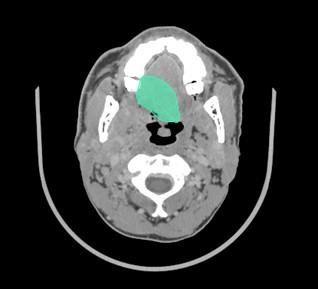

II. Cancer Diagnostics and Characterization using PET CT maging and Radiomics

We are able to characterize tumors' molecular propertiers such as gene variations and othegr characteristics such as a virus positivity, stage, grade, prognosis using PET CT data.

Our student working on cancer has received FULLBRIGHT award to conduct and continue our planned research in a prominent US lab.

She is presently in the USA and working on the heterogeneous analysis of H&N tumors with top international colaborators.

Our international journal publication on H&N Cancer has been selected as editor's choice.

Altinok, O. and Guvenis, A., 2023. Interpretable radiomics method for predicting human papillomavirus status in oropharyngeal cancer using Bayesian networks. Physica Medica, 114, p.102671.